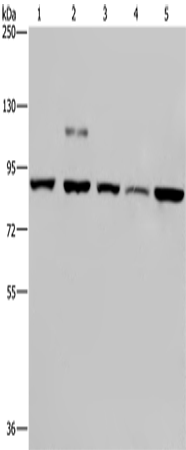

分类: 科研抗体货号: P05181别名: ESA; PON; MVCD5应用: WB,IHC反应种属: Human, Mouse, Rat